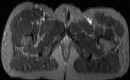

Visible Human male: Sectio transversalis 1926

CT

NMR

Pd                          / T2 \                         T1